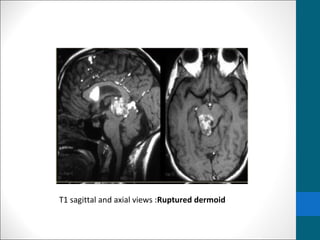

T1 sagittal and axial views :Ruptured dermoid

T1 sagittal andaxial views :Ruptured dermoid